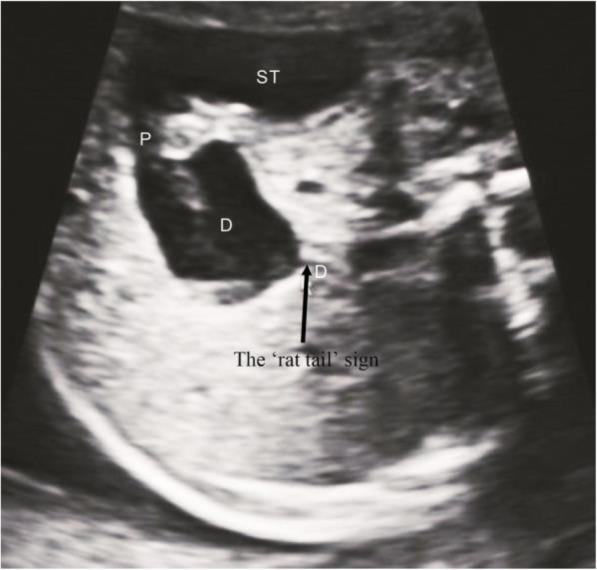

The results showed that there were 17 patients (42.5%) of congenital duodenal diaphragm, all with a 'rat tail' sign on the ultrasound images. Moreover, there were 4 patients (10.0%) of CDO caused by annular pancreas, all with a 'pliers' sign on the ultrasound images. We summarized the imaging features of the 'rat tail' sign and the 'pliers' sign.

CONCLUSION

The main conclusion of this study was that the 'rat tail' sign could be used as an indirect ultrasound feature to diagnose duodenal diaphragm. The 'pliers' sign could be used as a direct ultrasound feature in the diagnosis of annular pancreas in CDO.

结果显示,有 17 例(42.5%)患者为先天性十二指肠隔膜,超声图像均显示“鼠尾征”。此外,有 4 例(10.0%)患者为环状胰腺引起的 CDO,超声图像均显示“钳子征”。我们总结了“鼠尾征”和“钳子征”的影像学特征。

结论

本研究的主要结论是“鼠尾征”可作为间接超声特征用于诊断十二指肠隔膜。“钳子征”可作为 CDO 中环状胰腺的直接超声特征。